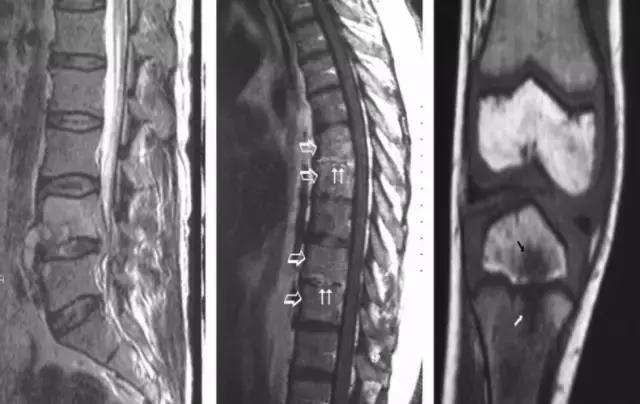

慢性「布鲁氏菌病」主诉症状有:间歇性背痛、关节痛、发汗、精神、神经症状和葡萄膜炎。随着病情进展,骨骼关节破坏慢慢呈现。虽然脊柱(尤其是腰椎)破坏较为常见,其他大关节、小关节骨骼破坏见诸报道。